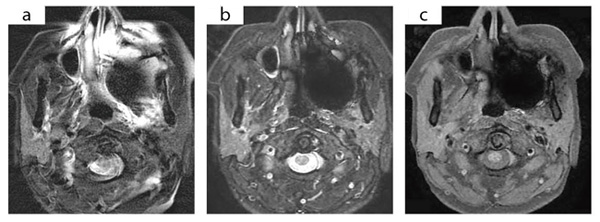

図1 IDEALによる頭頸部の脂肪抑制画像

右耳下腺の繰り返す腫脹と疼痛を主訴にMRI検査を依頼された。左上顎部の口腔内金属の影響で,従来の脂肪抑制T2強調像(a)では強いアーチファクトが生じ,脂肪抑制効果も不十分である。IDEALを用いた脂肪抑制T2強調像(b),T1強調像(c)では,アーチファクトによる無信号域(←)があるが,均一な脂肪抑制が得られている。